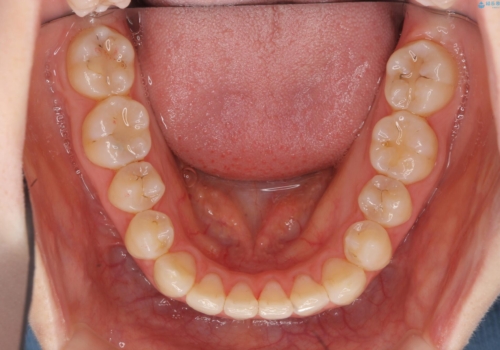

- 前歯の並びを主訴に来院。

マウスピースで歯を抜かずに治療しています。

左上の前歯が飛び出しており、唇が笑った時に引っかかっていたのが解消しています。

左上の前歯は小さいため、(矮小歯)左右対称になるようにセラミックで形を修正する治療も併用しています。

歯を大きくかぶせるスペースを作るため、右上の奥歯を後ろに下げています。

左にずれていた上の正中も揃い、大変喜んでいただきました。